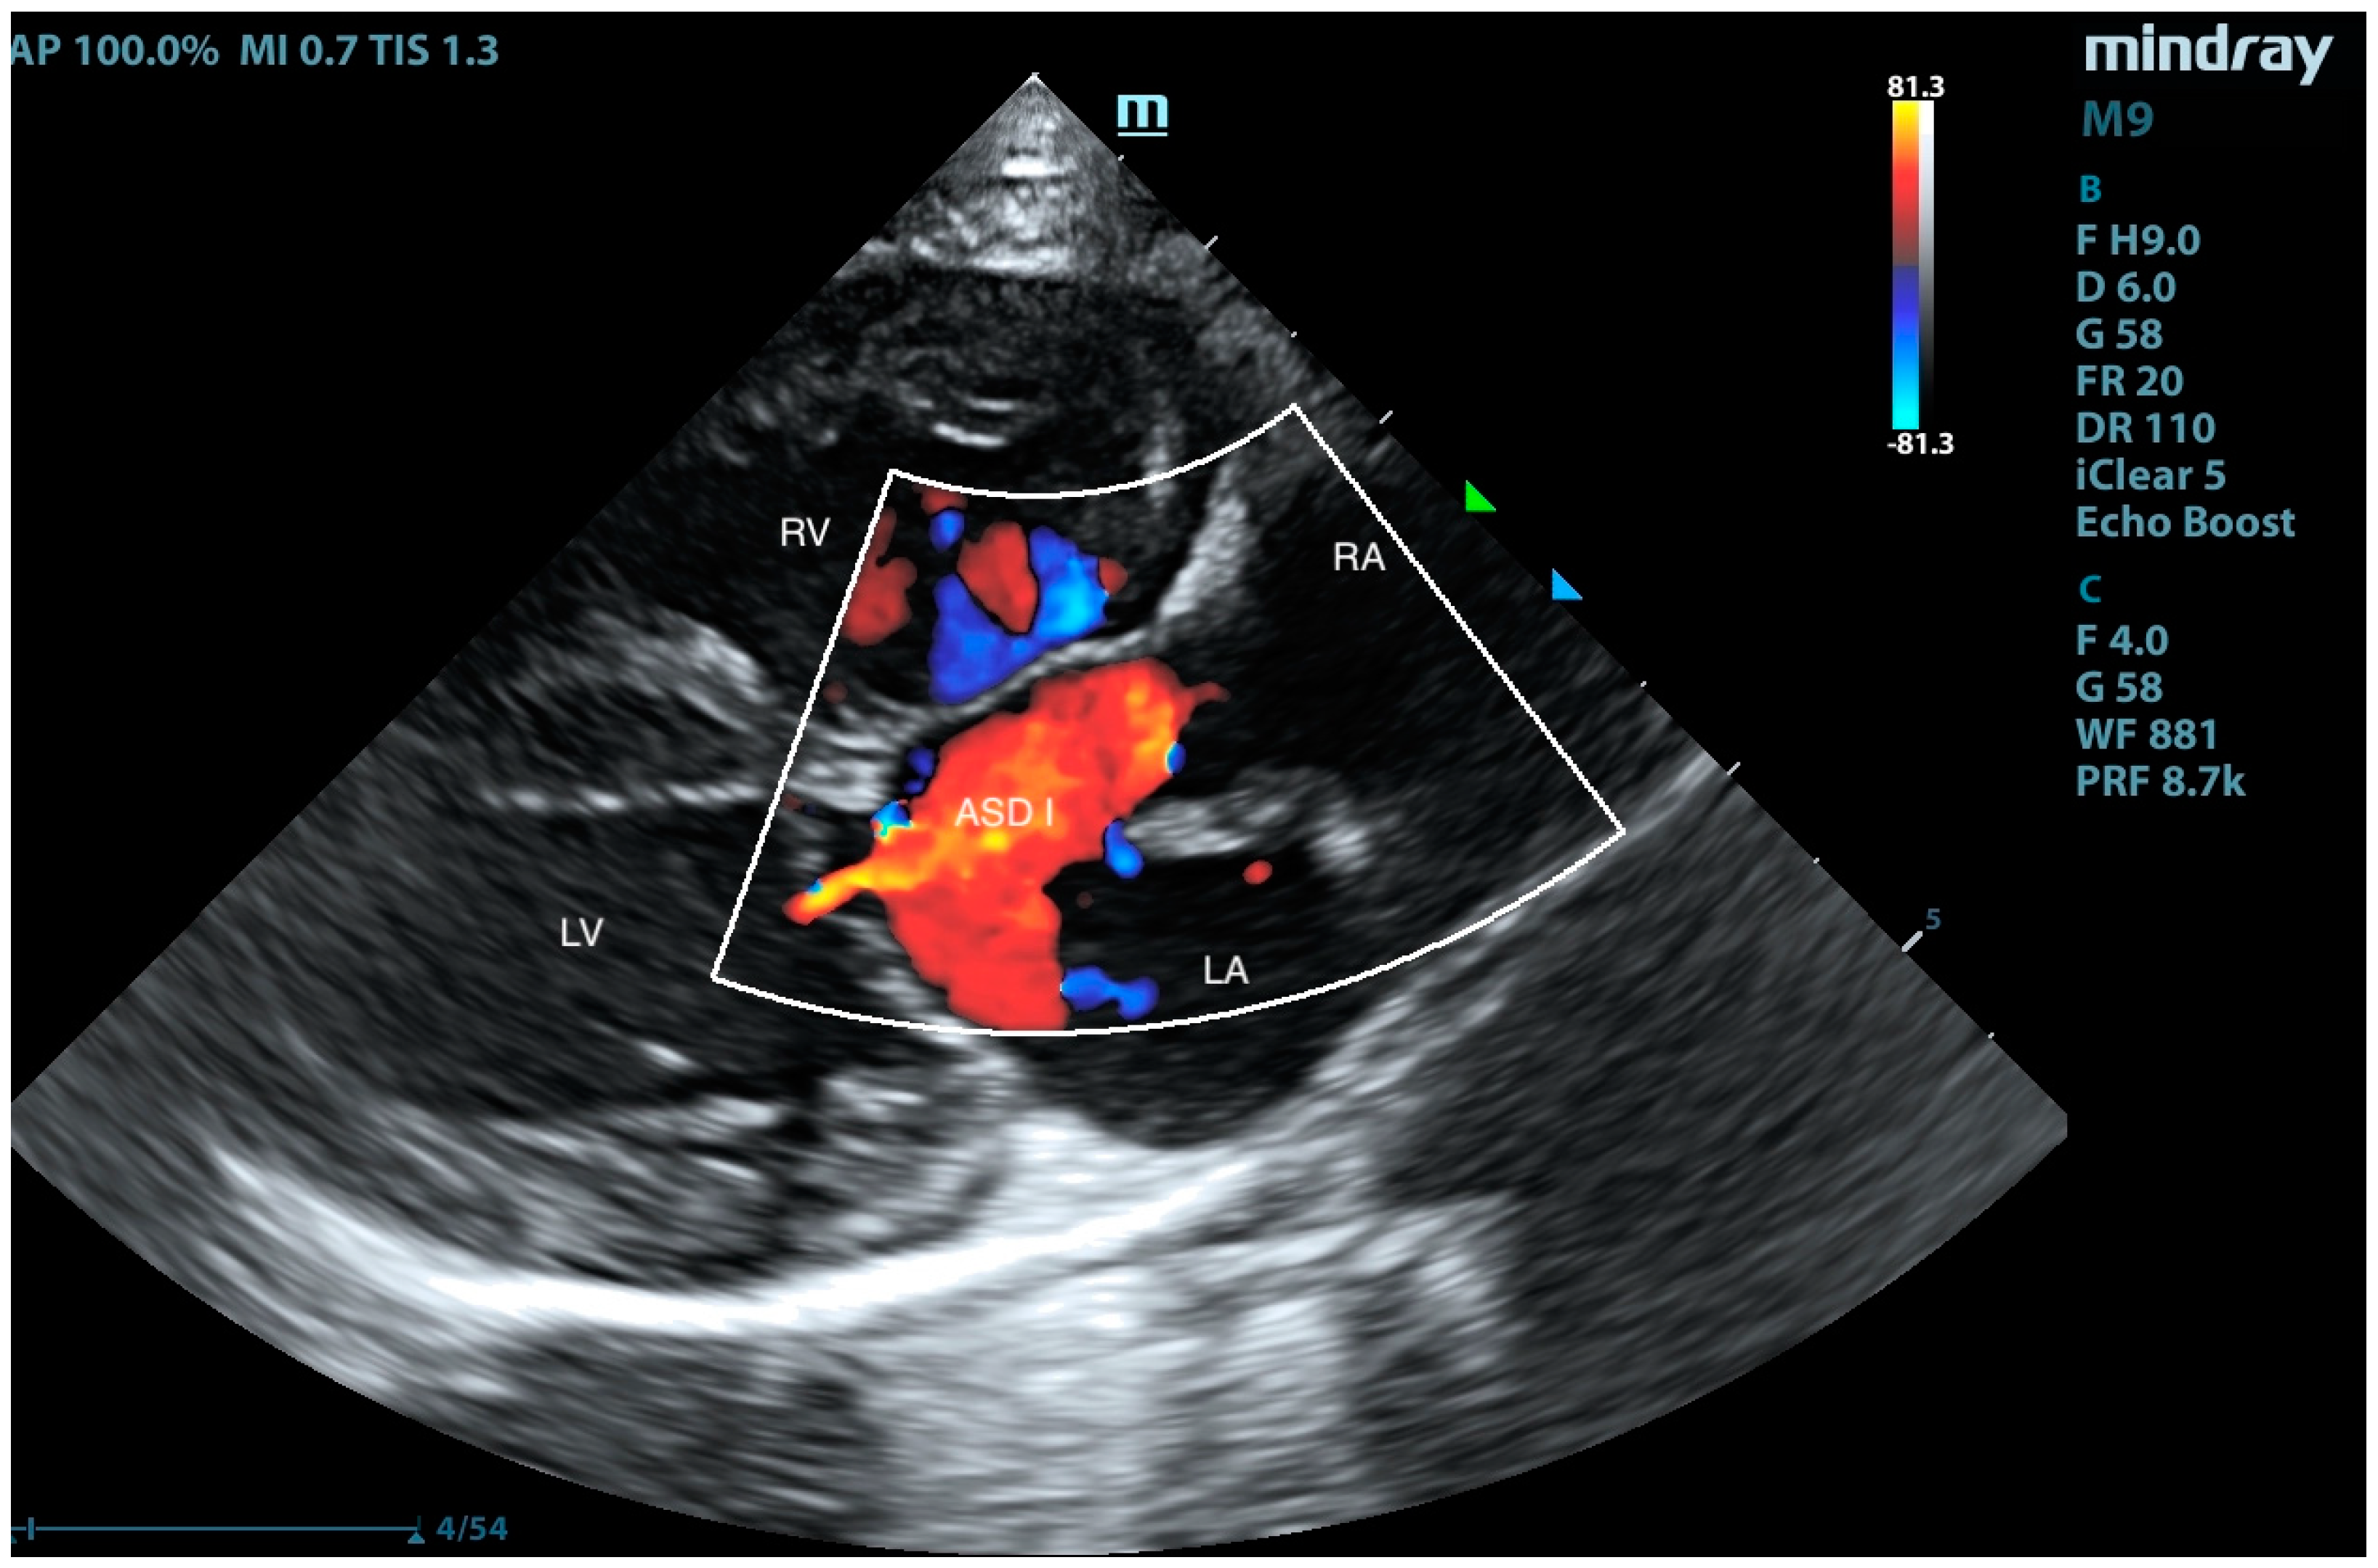

Pulmonary Artery Banding in a Cat with Atrioventricular Canal Defect Type A with Concurrent Muscular Septal Defect

2. Case Presentation